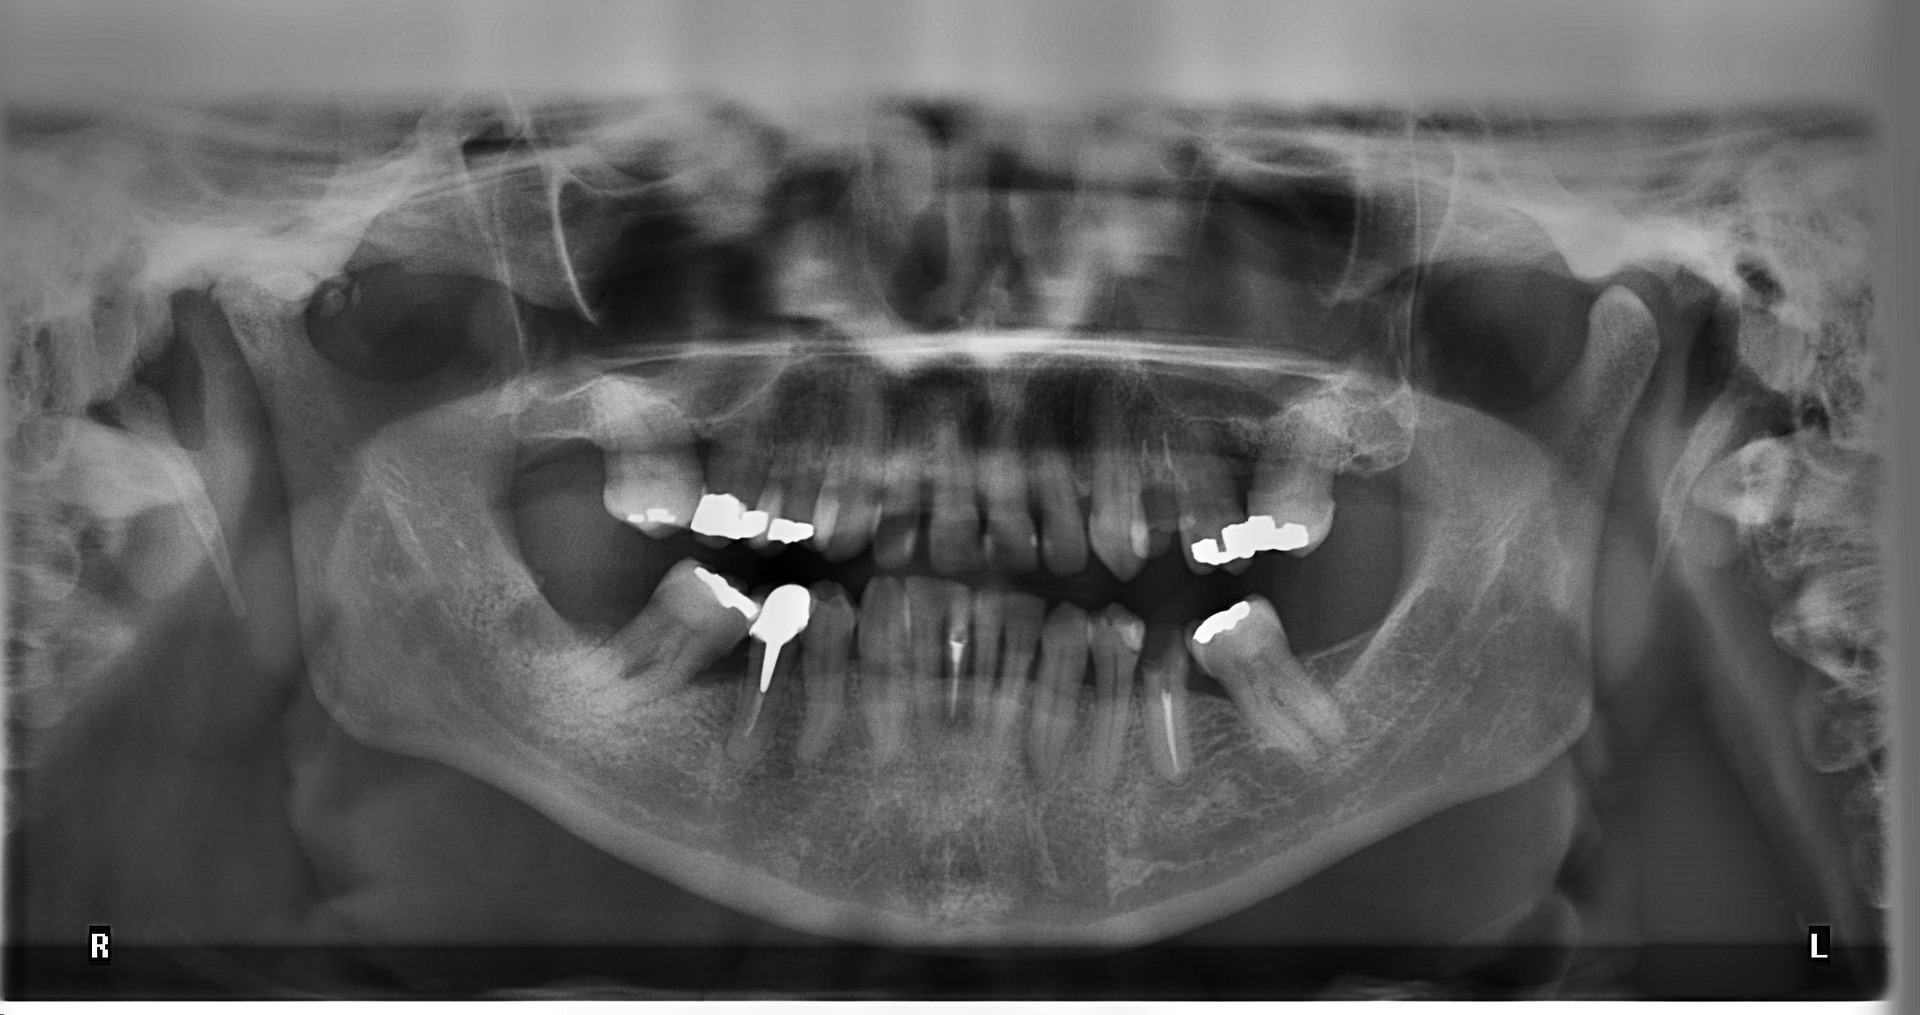

- Panoramic: These x-rays are generally used to determine whether patients have any issues with their wisdom teeth or jaw. You may also receive panoramic x-rays if you are planning to have dental implants.